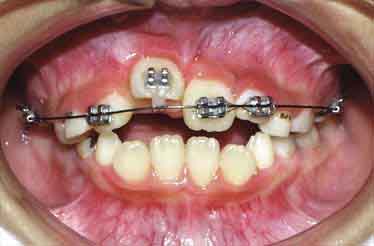

治療開始1年後